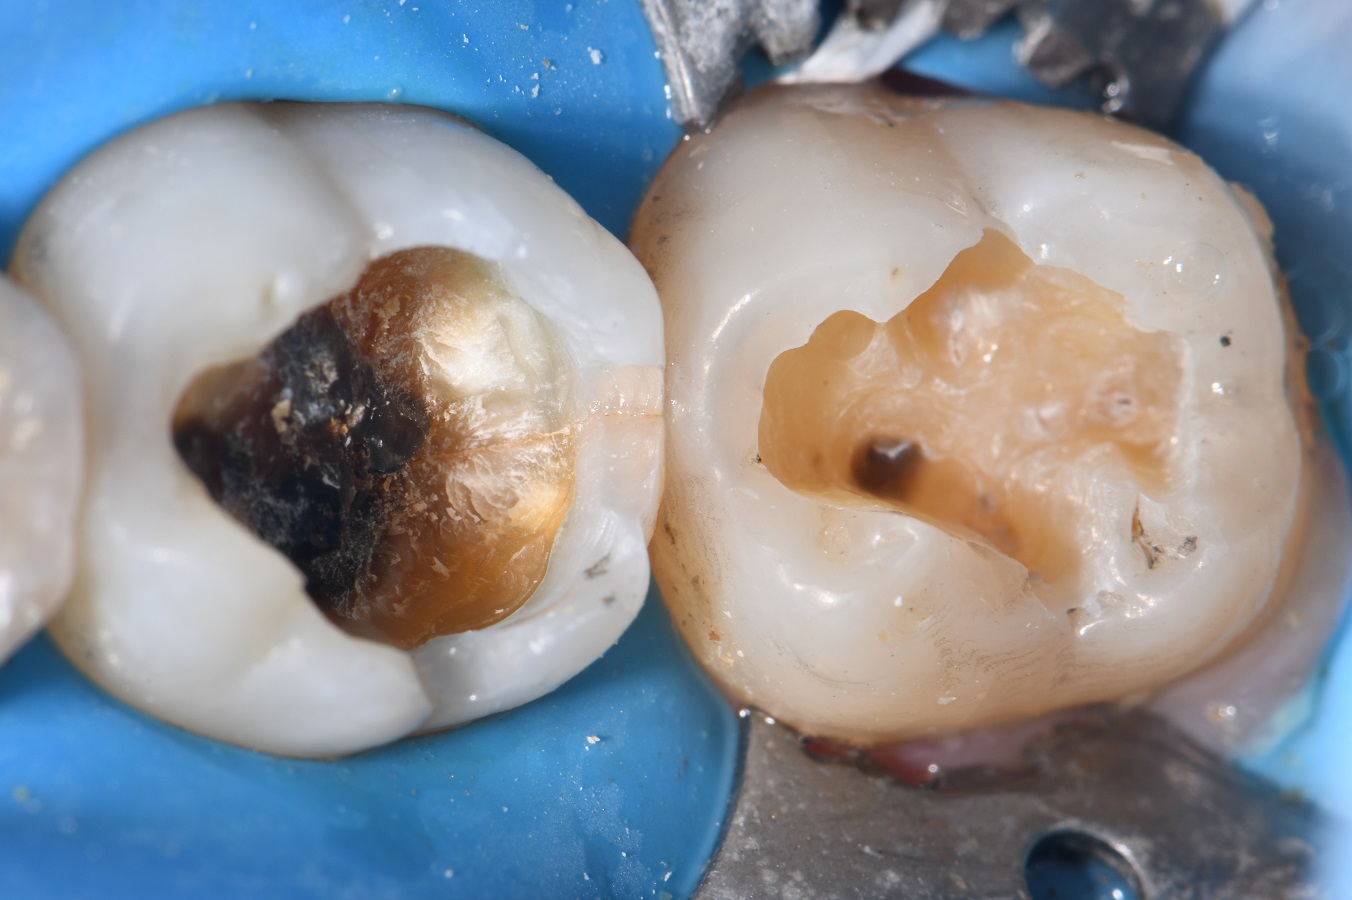

From www.clarencetam.co.nz

Chasing Hairline Fractures in Molars Hairline Fracture Tooth Symptoms The symptoms of a hairline cracked tooth can be subtle, but there are signs you can watch for, including: If you experience pain or discomfort when consuming hot or cold foods or drinks, this could be a sign of a hairline fracture. If these cracks don’t affect appearance and don’t produce pain, your doctor may advise leaving them alone. Not. Hairline Fracture Tooth Symptoms.

Chasing Hairline Fractures in Molars Hairline Fracture Tooth Symptoms The symptoms of a hairline cracked tooth can be subtle, but there are signs you can watch for, including: A hairline crack in a tooth, also called a craze line, is a superficial crack in the enamel, which is the tooth’s protective coating. If you experience pain or discomfort when consuming hot or cold foods or drinks, this could be. Hairline Fracture Tooth Symptoms.